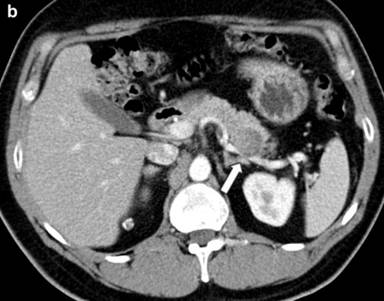

Further etiological investigations were performed, including an abdominal CT which showed a solid mass of 40 mm of diameter with small parietal eccentric calcification located in the body-tail of the pancreas (Figure 1a), encompassing the splenic artery (Figure 1b). Lymph nodes along the small gastric curve, in the inter-aortic and left para-aortic cable, and a calcified lymph node in the lower edge of the liver were also present (Figure 2). No alterations of the other parenchymal organs were detected. A suspicion of pancreatic cancer was pose, although the CA 19-9 was negative (1.6 U/mL; reference range: 0-37 U/mL).

Figure 2. Calcified lymph node in the lower edge of the liver. |